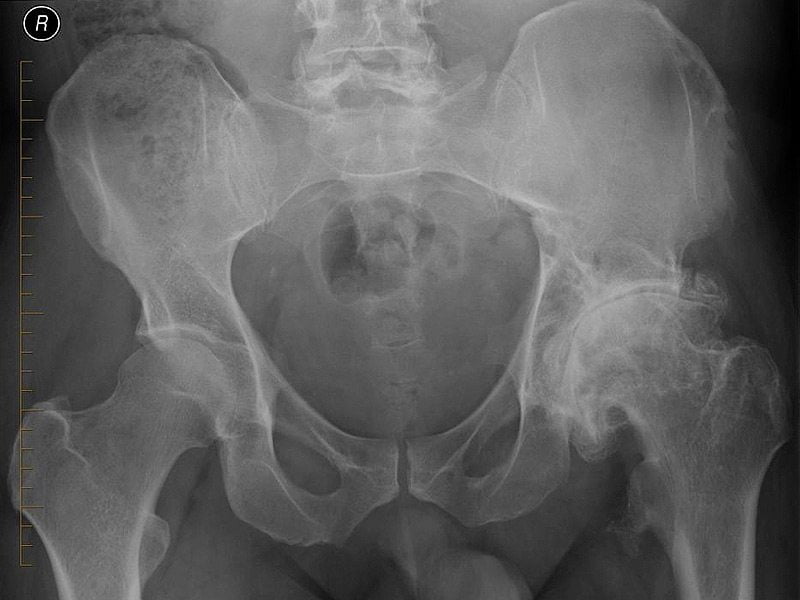

Остеоартроз тазобедренного сустава 1 степени, лечение которого будет эффективно медикаментозным путем, не провоцирует острых симптомов; мало кто из пациентов сразу обращается к врачу. Это влечет запускание болезни и переход ее в следующую степень протекания. На снимках рентгена еще не сильно заметны нарушения.

Остеоартроз тазобедренного сустава 2 степени характеризуется выраженным уменьшением пространства в суставной щели. В таком состоянии хрящи уже сильно повреждены, что провоцирует постоянное трение костей при движении и выраженную боль у пациента. Из-за развития отечности сустав теряет свои функции.

Выявить 2-ю степень несложно, так как при первом же рентгеновском снимке врач заметит существенные отклонения. Характерные признаки второй степени заболевания: